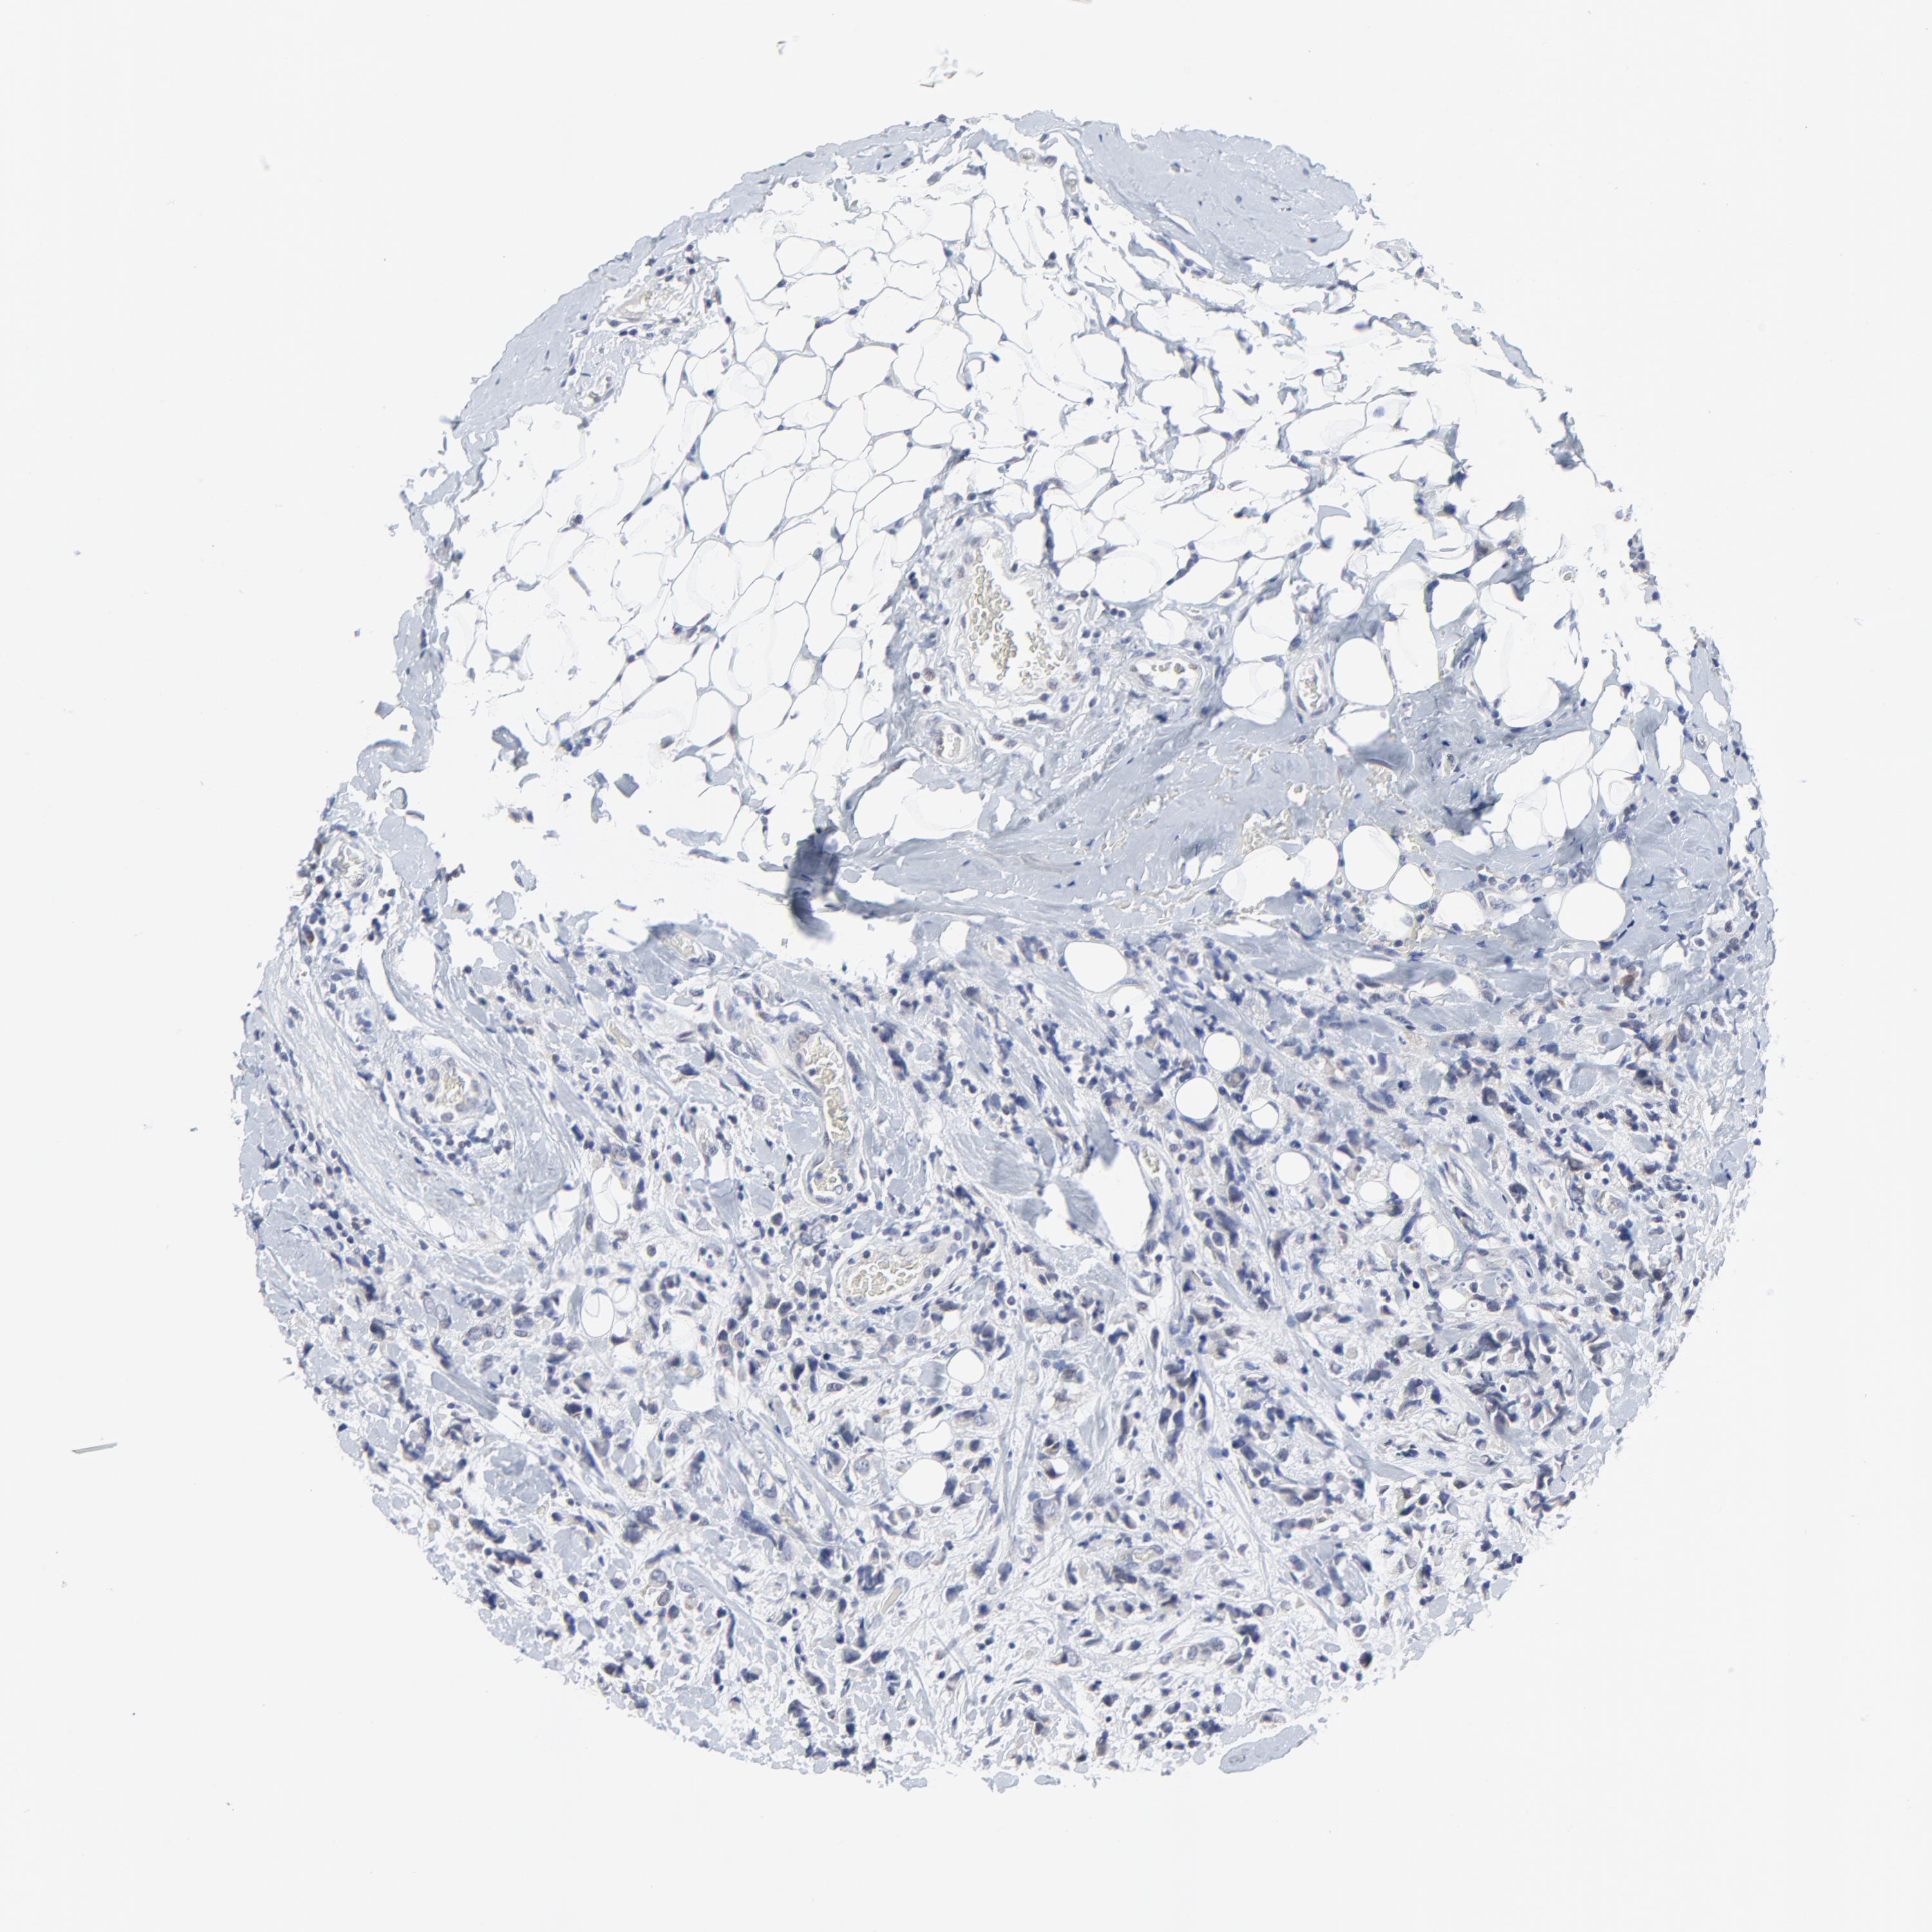

CANCER BREAST CANCER Show tissue menu

BRCA TCGA BRCA VALIDATION PROTEIN EXPRESSION

Breast cancer

Human cancer